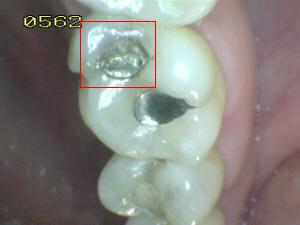

¿Determine los códigos pertinentes a cada imagen?

Click en el hipervínculo: Para comparar el resultado de su diagnóstico